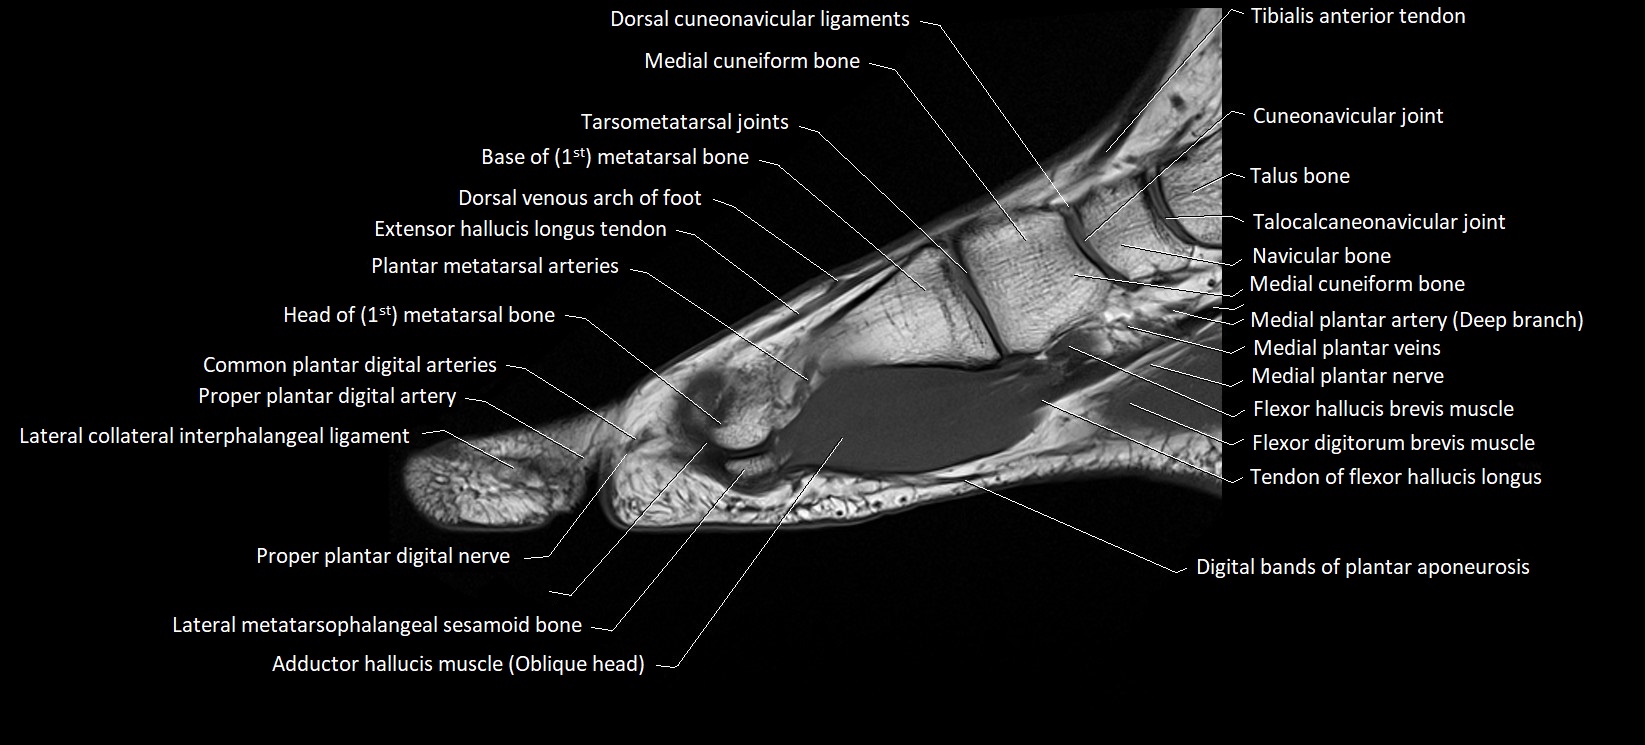

MRI image